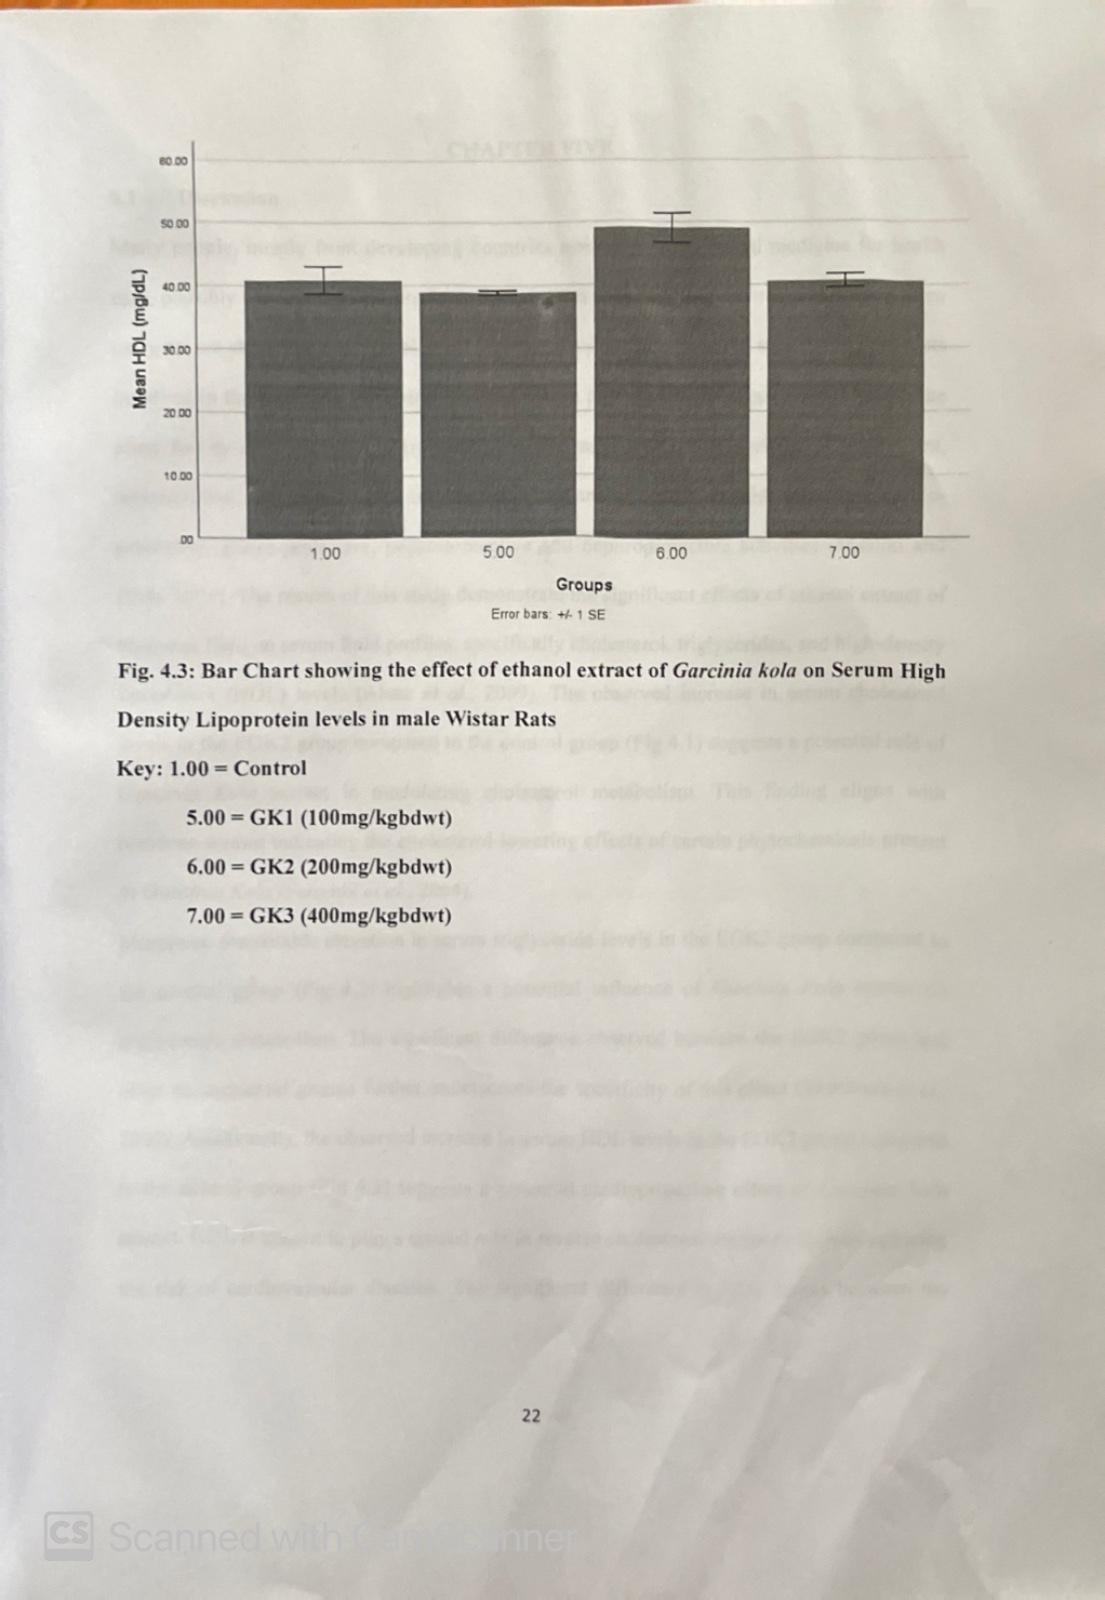

Carcass Characteristics of Broiler Chickens Fed Graded Level of Bitter Kola (Garcinia Kola) in Sokoto Semi-Arid Ecology